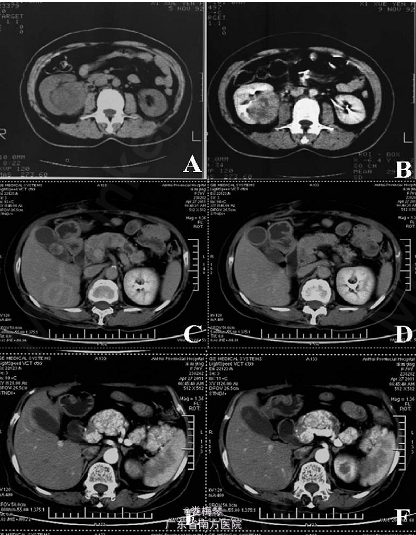

体查未见明显异常。2011 年4 月27 日上腹部双期CT 提示胰体尾病灶,结合临床有转移癌可能;胆囊结石;肝脏左叶外侧段小囊肿;右肾缺如(图1)。5 月3 日上腹部彩超提示:胰体见一6.0 cm×2.7 cm×4.2 cm不均质较低回声区,边界清,规则,血供丰富,诊断胰体尾部实质性肿瘤;胆囊结石;左肝囊肿。

临床诊断:胰体尾部占位;右肾切除术后。 于2011年5 月15 日在全麻下行剖腹探查术,术中探查见无明显腹水,上腹部粘连明显,肿块位于胰腺颈部和体尾部,最大病灶5cm×5cm,质硬,周围淋巴结无明显转移,胆囊慢性炎性改变,胆囊内扪及结石,肝脏质软,未见转移灶,遂行胰体尾+ 脾+胆囊切除术。 术后病理诊断为:胰腺转移性肾透明细胞癌。